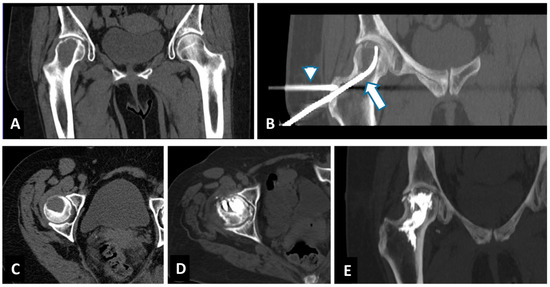

2.2. Radiofrequency Ablation (RFA) and Cementoplasty Procedure